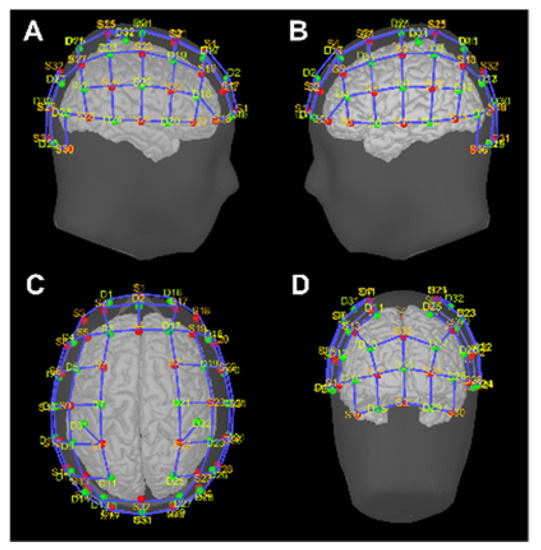

The focus of this study is on the analysis of the forward problem and the impact of SSA variability, ahead of the regularization implied by the inverse solution. Nonetheless, application examples of fNIRS cortical mapping are shown on representative subjects performing a motor task. Data were acquired using a continuous-wave system at λ = 760 nm and λ = 850 nm wavelengths (NIRScoutX 32 × 32, NIRx Medizintechnik, Berlin, Germany) that employs 32 LED sources and 32 avalanche photodiode detectors placed according to the international 10/5 EEG system (Figure 1). Source and detector pairs were combined into a total of 102 measurement channels.

The optodes were placed on the scalp at the subject’s MRI-native coordinates and a virtual 10/5 cap model was co-registered to the specific anatomy, assuring the correspondence of the relevant landmarks. The resulting grid of sources (red) and detectors (green) is shown in Figure 1.

The A 2 Ch % values were analyzed on a representative set of Brodmann areas (BA) (Figure 2A–D panels): bilateral BA1–2–3–4 as primary sensorimotor cortex (SensoriMotor Network, SMN), BA17 as primary (Visual Network 1, VIS1), and BA18-19 as secondary visual areas of occipital cortex (Visual Network 2, VIS2), BA46-9 as high-level, and BA45-47 as low-level sites of executive functions of dorsolateral– (PFC1) and ventrolateral–prefrontal cortex (PFC2), respectively. The correspondence between BAs with anatomical areas, along with the notation employed in the results section, is presented in Table 2.

We also considered the bilateral precentral and postcentral gyri as additional anatomical parcellations on the Destrieux atlas [45] (Figure 2E–G panels). Separate analyses of the selected BAs and Destrieux areas were performed. In both cases, A 2 Ch % values above a threshold of 0.2 are presented and considered as significant channel-wise values (i.e., at least of 20% of the sensitivity profile of the considered area is explained by that channel), while empty channels (i.e., those distant from any considered areas) are omitted.

Figure 1. (AD) Graphical representation of NIRS source (S, red dots) and detector (D, green dots) positioning over scalp surface ((A)—right hemisphere view; (B)—left hemisphere view; (C)—superior view; (D)—occipital view).

Figure 2. (AD) Cortical parcellations according to Brodmann areas on Colin27 atlas: BA1-2-3-4 (green), BA17 (light violet), BA18-19 (orange), BA45-47 (red), and BA46-9 (dark violet). (EG) Cortical parcellations according to Destrieux on Colin27 atlas: precentral gyrus (dark blue) and postcentral gyrus (light blue). White dots indicate channel positions over scalp surface.